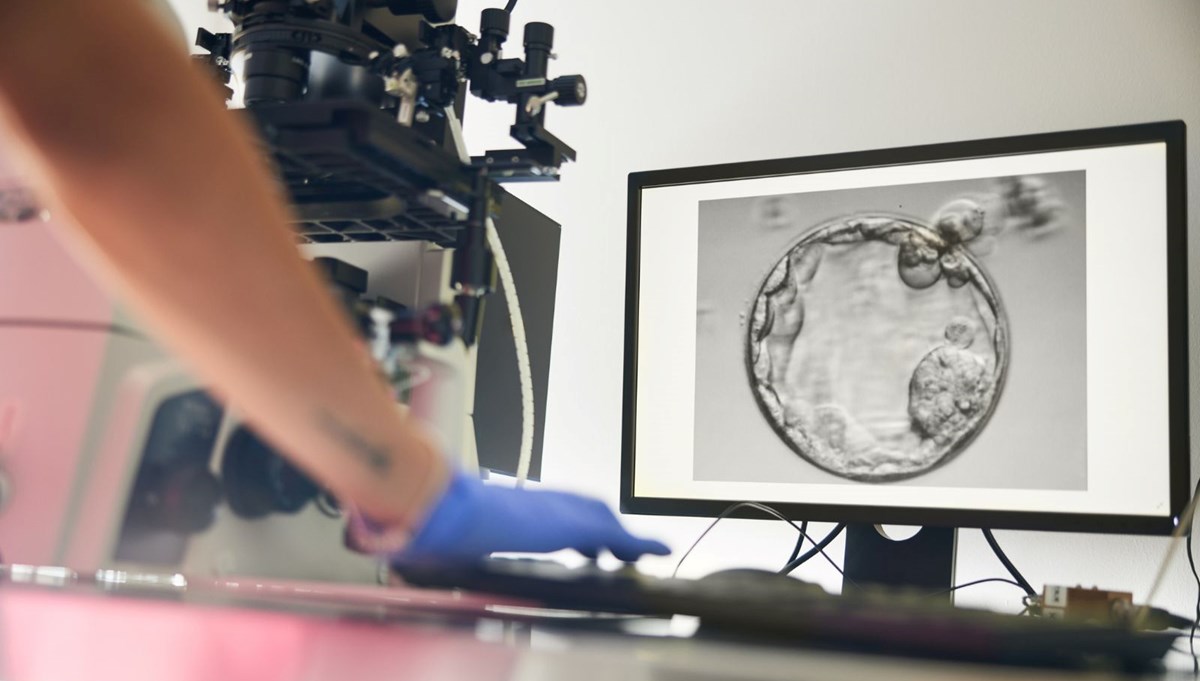

Nature Communications dergisinde yayımlanan araştırmada, bilim insanları sıradan bir insan deri hücresinin çekirdeğini (genetik bilginin büyük bölümünü taşıyan yapı) alıp, çekirdeği çıkarılmış bir donör yumurtaya aktardı.

Bu yöntemle 82 işlevsel insan olgunlaşmamış yumurta hücresi üretildi ve laboratuvar ortamında döllenme sağlandı.

Araştırma ekibi, doğal hücre bölünmesini taklit ederek fazla kromozomları ayıklayan ve geride 23 kromozom bırakan bir yöntem geliştirdi. Bu sürece “mitomeyoz” adı verildi. Ancak üretilen yumurtaların yalnızca yüzde 9’undan daha azı, döllenme sonrası embriyo gelişiminin kritik aşaması olan blastosist evresine (5–6 günlük gelişim) ulaşabildi. Üstelik ortaya çıkan tüm embriyolar kromozom bozuklukları taşıyordu.